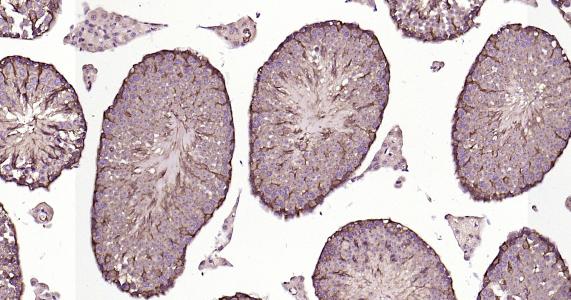

Paraformaldehyde-fixed, paraffin embedded Human Testicles; Antigen retrieval by boiling in sodium citrate buffer (pH6.0) for 15 min; Antibody incubation LC3B Monoclonal Antibody, Unconjugated(bsm-60842R) at 1:200 overnight at 4°C, followed by conjugation to the bs-0295G-HRP and DAB (C-0010) staining.

Paraformaldehyde-fixed, paraffin embedded Rat Testicles; Antigen retrieval by boiling in sodium citrate buffer (pH6.0) for 15 min; Antibody incubation LC3B Monoclonal Antibody, Unconjugated(bsm-60842R) at 1:200 overnight at 4°C, followed by conjugation to the bs-0295G-HRP and DAB (C-0010) staining.

Paraformaldehyde-fixed, paraffin embedded Mouse Testicles; Antigen retrieval by boiling in sodium citrate buffer (pH6.0) for 15 min; Antibody incubation LC3B Monoclonal Antibody, Unconjugated(bsm-60842R) at 1:200 overnight at 4°C, followed by conjugation to the bs-0295G-HRP and DAB (C-0010) staining.